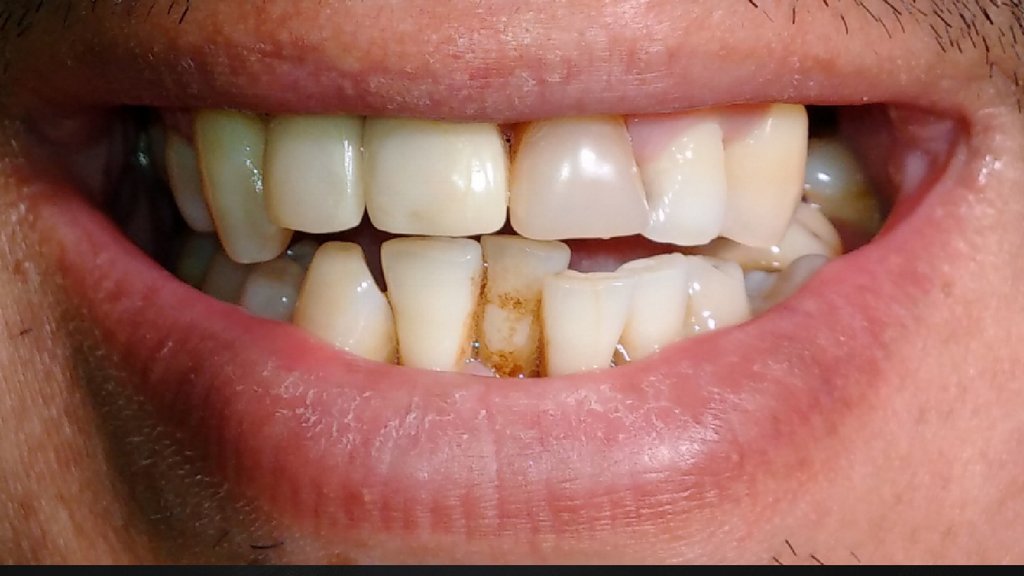

20.

Клиническая картина через 6 месяцев после имплантации.